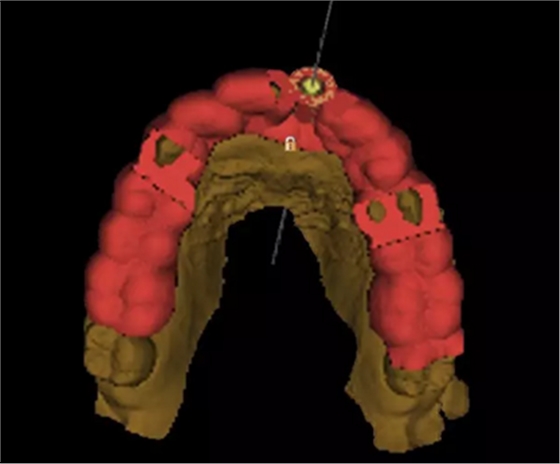

3.術(shù)前導(dǎo)板設(shè)計(jì)